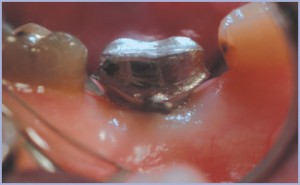

I tessuti condizionati in zona 15 alla rimozione del tappo di guarigione applicato al momento dell’inserimento dell’impianto (figg. 1,2). Si noti in particolare la salute e la quantità di gengiva aderente attorno al tappo (fig. 3). Viene presa un’impronta con il transfer, con tecnica sandwich. In questo caso si evidenzia la perfetta congruità dei tessuti intorno al transfer (fig. 4). La connessione transfer/impianto permette un facile e affidabile inserimento del moncone da impronta dentro l’impianto e la ritenzione del transfer all’interno dell’impronta (figg. 5-7). In laboratorio si costruisce una corona in composito adesa primariamente sul moncone in titanio. Questa tecnica è realizzabile solo con l’utilizzo di monconi di titanio pieni e di una connessione impianto/moncone conometrica (figg. 8-13). La corona integrata sul moncone è inserita direttamente dentro l’impianto (figg. 14,15).

Si noti l’evidente analogia del complesso moncone/corona con il dente naturale e la perfetta integrazione del restauro nei tessuti circostanti (figg. 16-18).